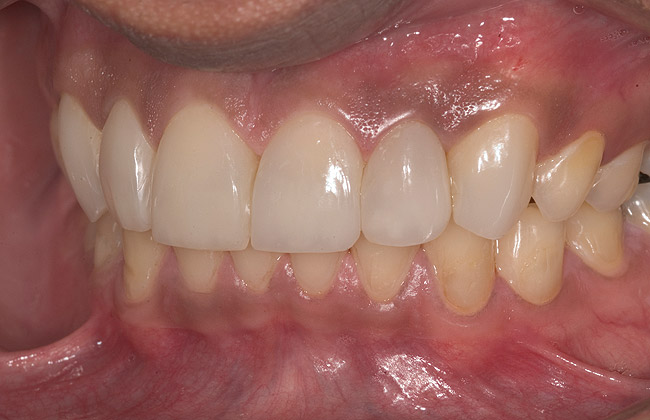

Figure 15  Maximum intercuspation (MIP) after restoration of the lost palatal anatomy.

Figure 15

Figure 16  1:2 right lateral view; posteriors discluded in MIP.

Figure 16

Figure 17  1:2 left lateral view; posteriors discluded in MIP.

Figure 17